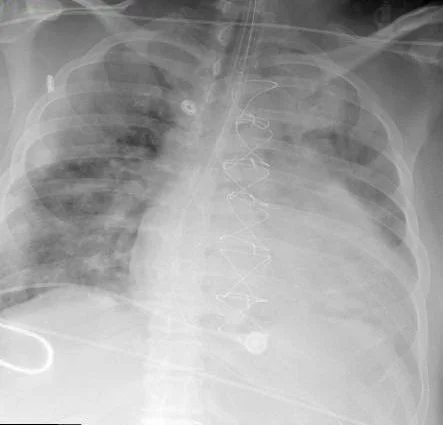

Kenneth is a 36yo 125kg male who presented to an outside hospital with SOB and fever. He was admitted and diagnosed with ARDS, pulmonary edema, and possible pneumonia based on his CXR. He was started on antibiotics and subsequently intubated for progressive hypoxemia. He has a history of hypertension and had an aortic valve replacement with an allograft about 10 years ago for endocarditis. The Transthoracic Echo showed a EF of 60-65%, and identified no valve abnormalities. He was transferred to your center for possible ECMO for his respiratory failure. On arrival in the ICU, your ICU team makes some vent adjustments switching him to Bi-level and successfully stabilize him with a saturation of 90-94%, and with reversal of his respiratory acidosis, but over the next 12 hours he deteriorates again. Cardiology is called for possible heart failure, and renal for his renal dysfunction. Once they have collected the data below, they call you to discuss the possibility of ECMO support to stabilize his hemodynamics and gas exchange and prevent multisystem organ failure while a definitive plan is established including possible surgery.

Ventilator - RR 26, FiO2 100%, PIP 42 PEEP 15.

Exam - Bilateral decreased breath sounds and rales. Mild systolic murmur, III/VI diastolic murmur. Weak peripheral pulses.

ABG - 7.34, pCO2 50, pO2 79, Bicarb 27, B.E. 0, O2Sat 95%. Lactate 3.5.